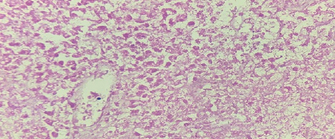

Immunohistochemical staining for Cytokeratin 7, demonstrating the diffusely infiltrating carcinoma in the submucosa, muscular wall, mesenteric adipose tissue, and serosa (Courtesy Dr. V. Penopoulos)